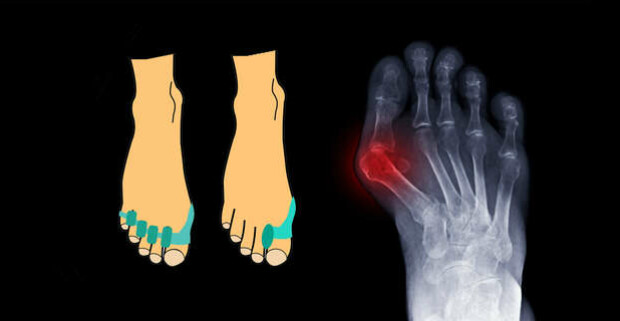

Hallux Valgus chránič a korektor

Táto ortopedická pomôcka je prepojením silikónového korektoru a chrániča Hallux Valgus. Výsledok tohto spojenia rieši problémy vybočeného palca a citlivosti palcového kĺbu v obuvi. Vybočený palec môže byť genetická deformácia alebo nadobudnutá nosením nesprávnej obuvi s úzkou špičkou a vysokými opätkami, no môže sa objaviť aj po reumatických ochoreniach. Chránič a korektor je odporúčaný na nosenie každý deň v akejkoľvek obuvi. Pomôcka sa naťahuje na palec a je vhodné ju fixovať, aby sa pri celodennej chôdzi nehýbala.

Príznaky Hallux valgus

Viete správne rozpoznať príznaky vybočeného palca? V prvých štádiách budete pociťovať občasnú bolesť chodidla po boku a môžete vidieť jemné začervenanie. Postupom času bude dochádzať k oddeľovaniu kostičiek pod palcom a v tomto štádiu už rozpoznáte halux aj vizuálne. Palec sa bude postupne vybočovať smerom k ostatným prstom na nohe.

Ak budete tento problém ignorovať, môže váš vybočený palec ostatné prsty na nohe začať križovať a výsledkom budú permanentné bolesti. V tomto štádiu je chodidlo citlivé aj na menší dotyk. Posledným štádiom haluxu je, keď vás už lekár pošle s týmto problémom na operáciu. Preto netreba čakať a začnite s liečbou a prevenciou čo najskôr.